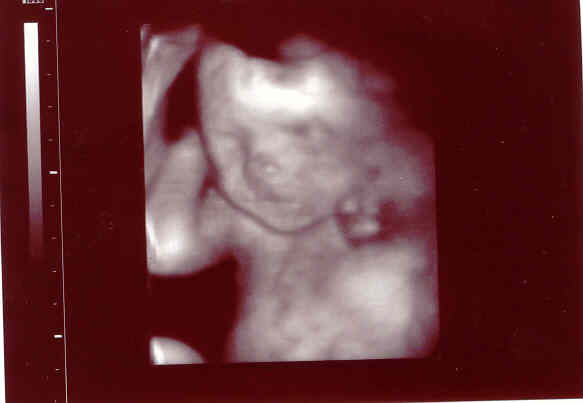

Én tegnap voltam 18 hetes genetikain ahol megerősítést kaptunk, hogy Dávidka Dávidka marad most már nincs mese

BPD:43mm THQ:39 mm ezeket mérték, az AFP értéke meg 1,21